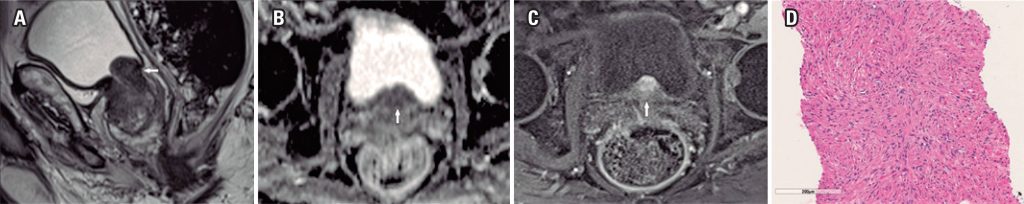

We found three pathologic proved cases of prostatic pure leiomyomas (0.02%) in our series and described the multiparametric magnetic resonance imaging features of these prostatic leiomyomas. The imaging findings had similar features to lesions with moderate or high suspicion for significant cancer (Likert 4 or 5) when localized both in the transitional zone or in the peripheral zone of the gland.

Pure prostatic leiomyomas had imaging findings on multiparametric magnetic resonance imaging that mimicked usual adenocarcinomas on this test. Radiologists, urologists and pathologists must be aware of this entity and its imaging features.